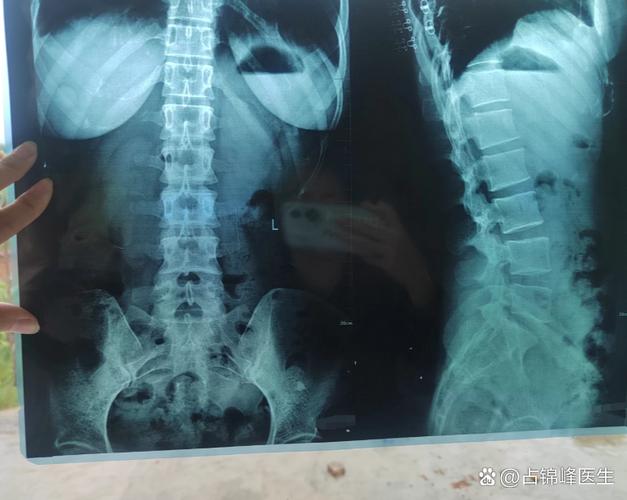

儿童强直性脊柱炎是一种好发于青少年的慢性、进展性、自身免疫性疾病,主要侵犯骶髂关节、脊柱和四肢大关节,导致关节炎症、疼痛、僵硬,并最终可能导致关节融合和强直。

- 脊柱强直和畸形:

- 脊椎骨之间逐渐融合,导致脊柱活动度越来越差,最终变得僵硬。

- 典型的“驼背”畸形(医学上称“驼背畸形”),头部前伸,无法平视前方。

- 胸廓活动受限,影响呼吸功能。